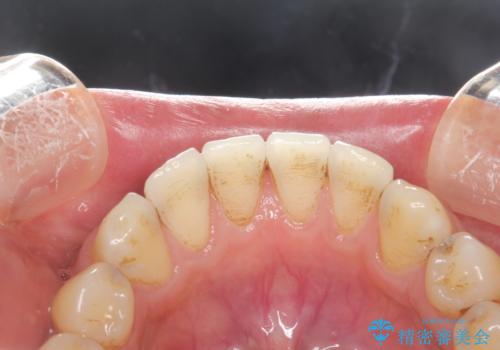

- 全体的な着色(ステイン)、黄ばみが気になるとのことで、来院されました。着色(ステイン)などの付着量が多かったためPMTCの60分コースを行いました。

PMTCを行うと、着色(ステイン)や歯石などを除去することができます。

PMTCは、歯科医院にて専門的な機械・材料を使用して行う専用クリーニングです。着色(ステイン)や歯石を取り除くことで、ご自身の本来の歯の色となります。また、施術後にはスッキリとした爽快感あ得られたり、歯の舌ざわりがツルツルになり気持ちがいいです。